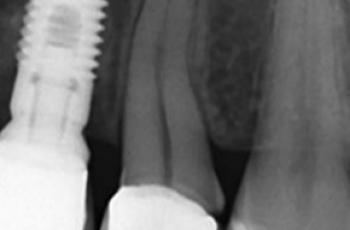

Tratamiento no quirúrgico de la periimplantitis. A propósito de un caso... Cirugía periodontal y periimplantaria | UIC Tratamiento no quirúrgico de la periimplantitis. A propósito de un caso... Se presenta el caso de una paciente de 58 años de edad, sin antecedentes médicos de interés y no fumadora. El motivo... Etiología, diagnóstico y tratamiento de la periimplantitis: Caso... Tto. Periimplantario | UV Etiología, diagnóstico y tratamiento de la periimplantitis: Caso... Presentamos nuevo caso clínico realizado por los doctores Manuel Rodríguez Aranda, Francisco... Efectividad del Tratamiento en Periodontitis Agresiva Tto. Periodontal | UIC Efectividad del Tratamiento en Periodontitis Agresiva El mantenimiento de la dentición natural en estado de salud ha sido un objetivo importante en... Injerto gingival libre alrededor de implantes dentales. A propósito de un... Cirugía periodontal y periimplantaria | UIC Injerto gingival libre alrededor de implantes dentales. A propósito de un... La cirugía mucogingival reconstructiva alrededor de implantes corrige los defectos de la... Terapia mucogingival en implantes: corrección de las secuelas mucosas de... Cirugía periodontal y periimplantaria | UV Terapia mucogingival en implantes: corrección de las secuelas mucosas de... El caso que se presenta a continuación muestra una resolución impecable de un defecto mucogingival... Importancia del mantenimiento en la evolución de un paciente con... Mantenimiento | UV Importancia del mantenimiento en la evolución de un paciente con... La periodontitis agresiva se define como una enfermedad de rápida progresión en la destrucción... Tratamiento de Recesiones Gingivales Clase III de Miller mediante técnica... Cirugía periodontal y periimplantaria | UIC Tratamiento de Recesiones Gingivales Clase III de Miller mediante técnica... El caso clínico que presentamos a continuación es el de una paciente que acude a la consulta... Tratamiento de un paciente con periodontitis crónica moderada generalizada Tto. Periodontal | UIC Tratamiento de un paciente con periodontitis crónica moderada generalizada El caso clínico que se presenta a continuación, muestra el tratamiento de una paciente...